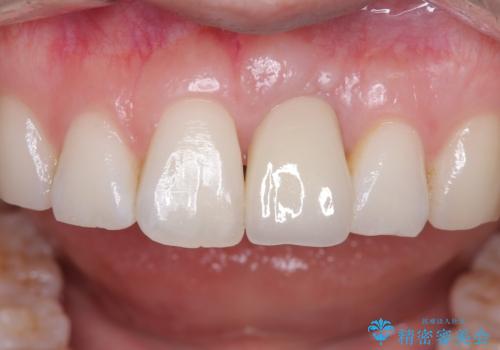

- 金属を外してセラミックを入れたいことを主訴に来院された患者さんです。

セラミックインレーにて修復を行いました。

当院でのセラミックインレーは、ラバーダムを使用して装着しております。